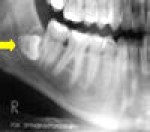

Observe a radiografia abaixo e classifique o dente incluso (48), segundo Pell e Gregory (1933).